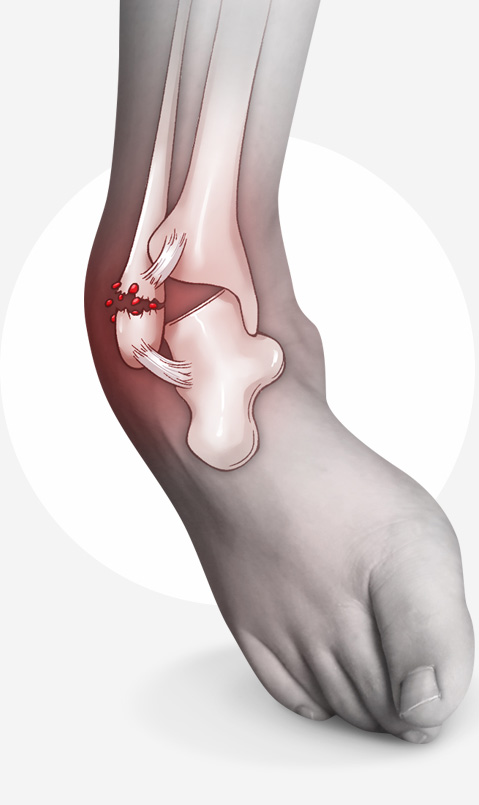

발목 염좌, 골절, 탈구 등 급성 외상으로 인해 연골이 손상될 수도 있으며, 과도한 사용으로 인해 발목 관절에 반복적인 충격이 가해지면

연골이 손상이 될 수 있습니다.